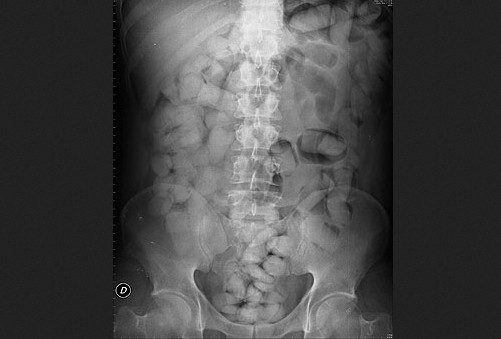

وأضاف المصدر ذاته، أنه تم عرض المشتبه فيها، على خبرة طبية لتفريغ الكبسولات الموجودة بأمعائها، وذلك في انتظار إخضاعها لبحث قضائي تحت إشراف النيابة العامة المختصة.